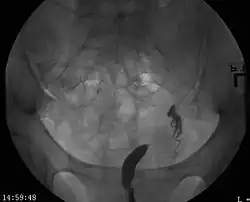

A unicornuate uterus as seen on a hysterosalpingogram | |

A unicornuate uterus represents a uterine malformation where the uterus is formed from only one of the paired Müllerian ducts while the other Müllerian duct does not develop or only in a rudimentary fashion. The sometimes called hemi-uterus has a single horn linked to the ipsilateral fallopian tube that faces its ovary.[1]

Helpful techniques to investigate the uterine structure are transvaginal ultrasonography and sonohysterography, hysterosalpingography, MRI, and hysteroscopy. More recently 3-D ultrasonography has been advocated as an excellent non-invasive method to evaluate uterine malformations.[4]